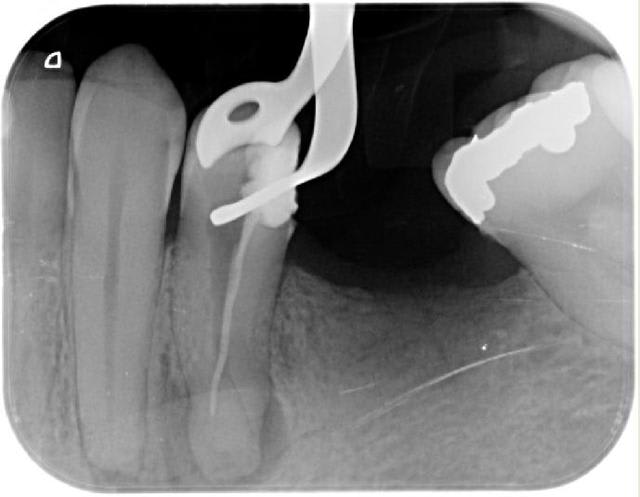

par provoc on s'est amusé à faire une photo

pour répondre à la question avec quoi j'obture : maitre cone et condensation verticale simplement

promis je ne polluerais plus les posts d'endo

cadeau (si je puis me permettre) de fin

mon objectif avait été de dire qu'on pouvait aussi faire simple mais la critique SYSTEMATIQUE me casse les c...